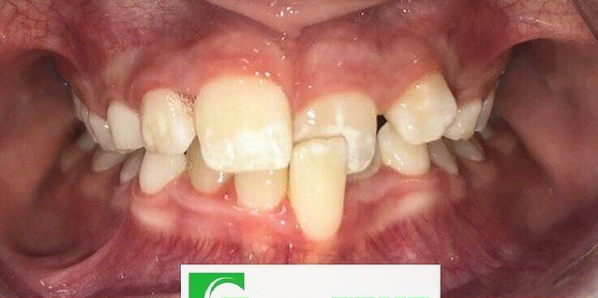

Врач Заводова (Рыбась) Анна Викторовна принимает в стоматологическом комплексе ПРЕЗИДЕНТ НА ЛЮБЛИНСКОЙ в Москве. Имеет рабочий стаж 21 год. Специализируется на ортодонтии, по которой клиника оказывает 3 услуги. Имеет 4 работы до/после в портфолио. Квалификация специалиста подтверждена 15 лицензиями, сертификатами и наградами. Для уточнения дополнительной информации о специалисте или записи на прием можно позвонить по телефону

Установка брекетов

Установка брекетов в Москве

от 200 000 ₽